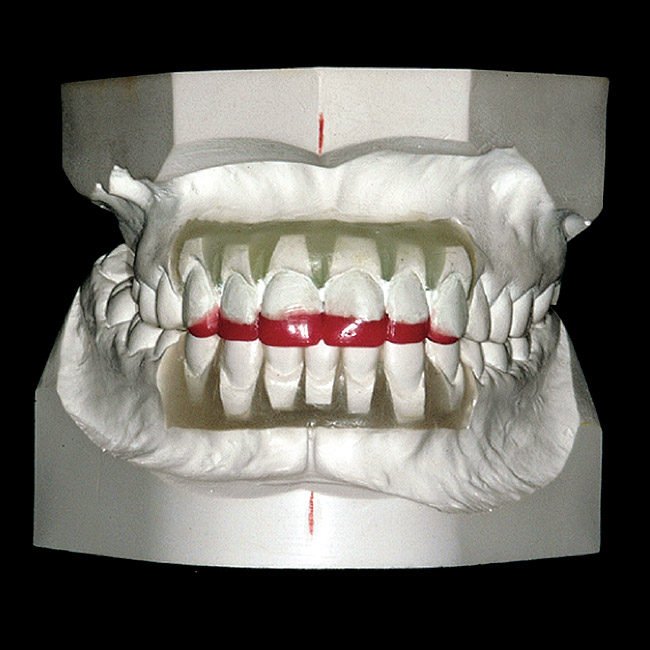

Figure 1  An example of an orthodontic set-up and diagnostic wax-up for a patient with severely worn anterior teeth.

Figure 1